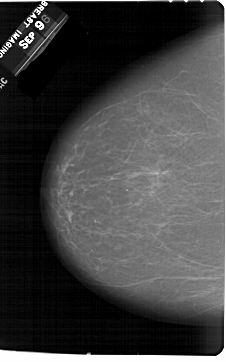

A_1354_1.LEFT_MLO

LEFT_MLO LINES 6871 PIXELS_PER_LINE 4141 BITS_PER_PIXEL 12 RESOLUTION 43.5 NON_OVERLAY